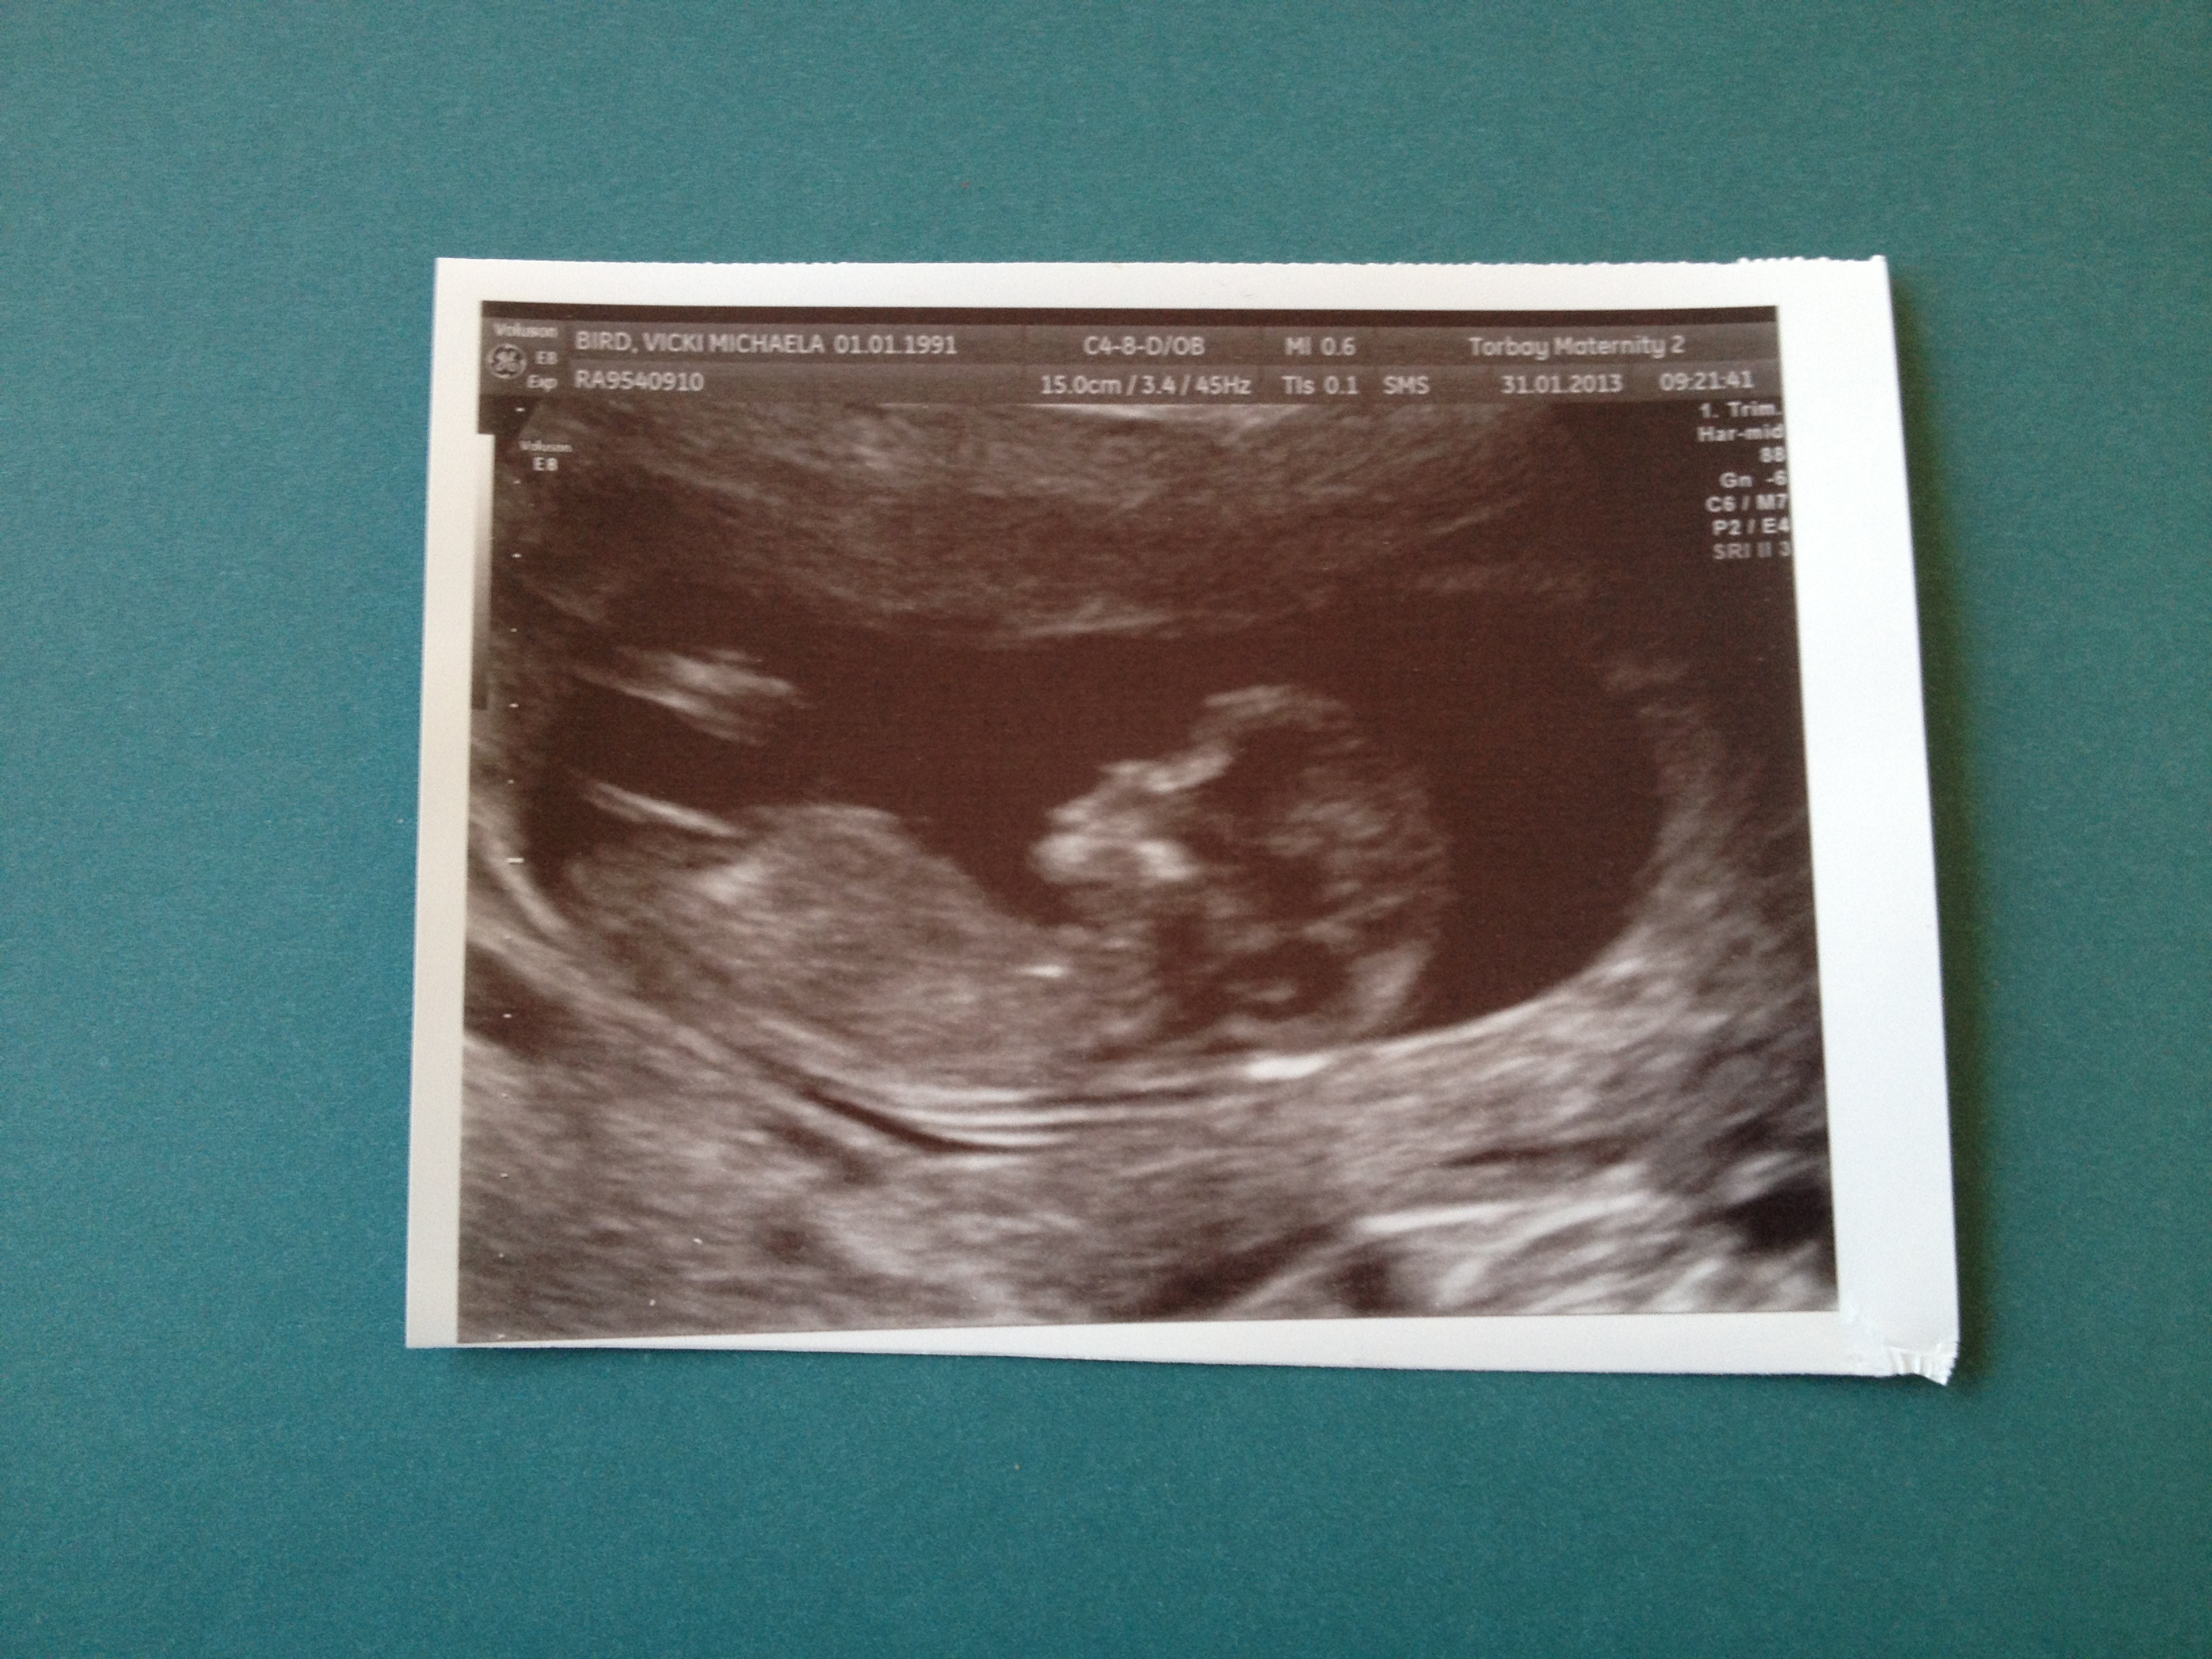

Please guess ladies :) and if you wish, give a reason why you think what you do :) xx

Very girly nub :) Looks like same as my, nub is even pointing a bit down! Do you have any preference?

Classic girl nub. This is what I am hoping to see next week